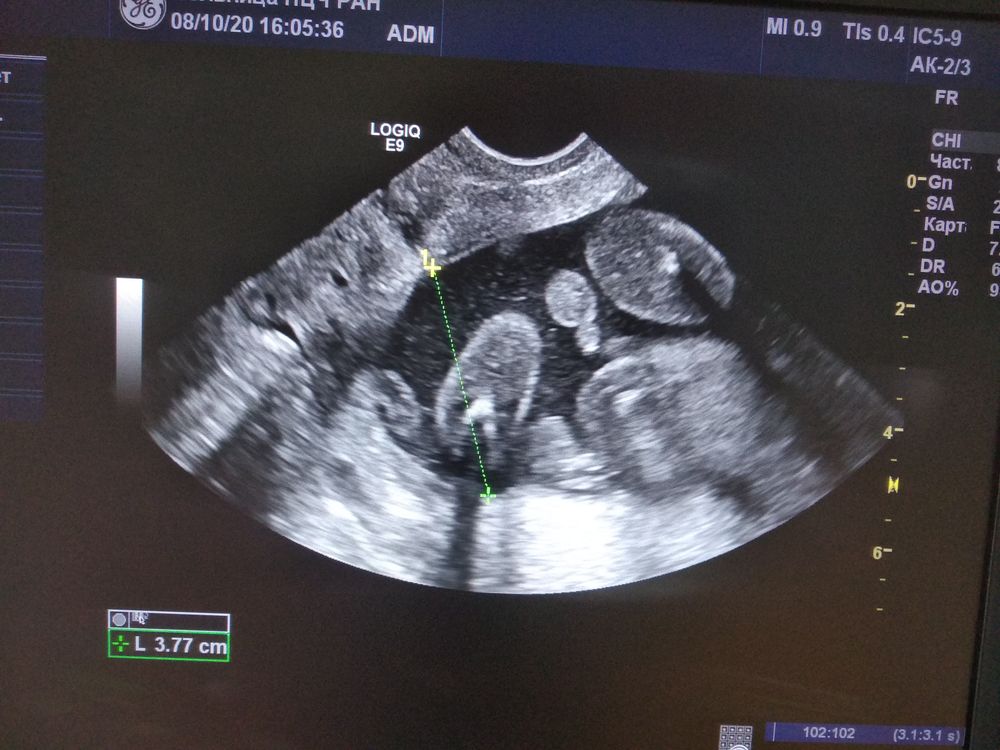

У нас мальчик

Пол малышаКак я ждала этого дня,как я хотела быстрее узнать,что у нас , ДЕВОЧКА,ну не знаю я,что делать с мальчиками

Сейчас 18 нед,малыш во всю пинается, но вот два дня назад по ощущениям сел на попу,это подтвердилось, теперь привет туалет

на фотке попка и между писюн с машонкой